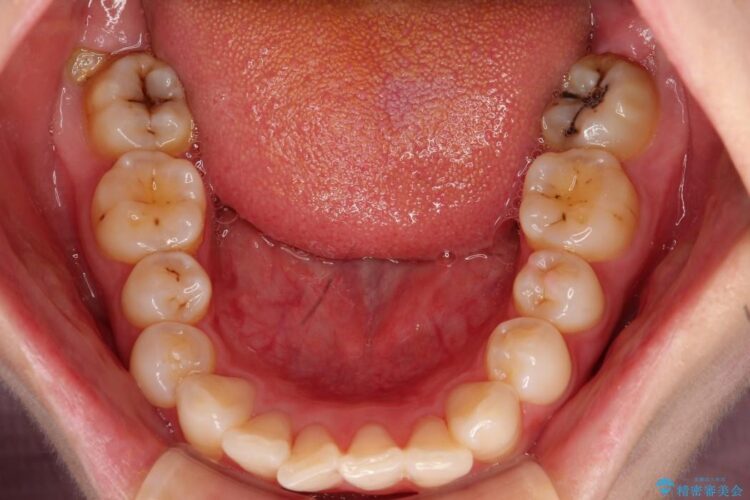

【20代女性】出っ歯の矯正 治療例

治療費の安い矯正治療を希望されていたため、メタルのワイヤー装置にて治療する計画にしました。また、歯みがきが苦手だったため、矯正治療をする前に徹底的にブラッシング指導を行いました。

出ている歯を引っ込めるためのスペースを作るため、上下左右の小臼歯を抜歯し、ワイヤー矯正を行いました。治療後は、口元がスッキリとしたことで患者様にも喜んでいいただきました。